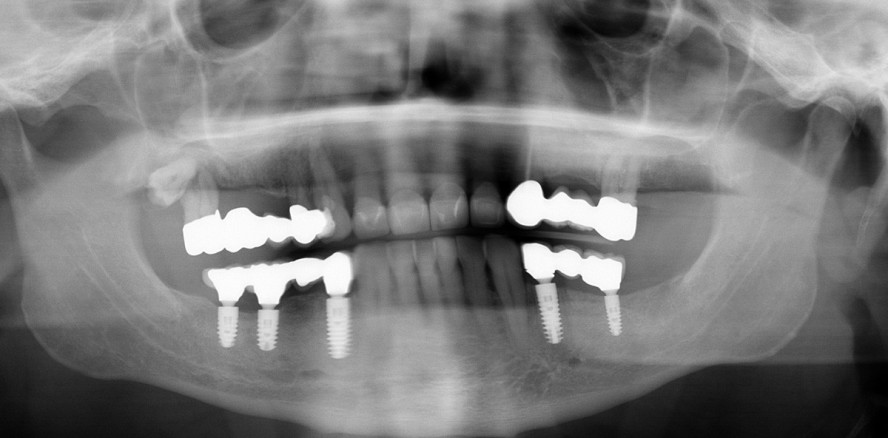

Fallbeispiel 1

Es kam bei einer Patientin zum Implantatverlust auf der einen Seite und Implantatfraktur auf der anderen Seite (Abb. 1) nach Versorgung nach dem SmartFix-Konzept durch Spannungen im CAD/CAM-Gerüst, da sich nicht rotationsgesicherte Aufbauten nach Stegherstellung lösten und nachträglich versucht wurde, diese wieder in Position zu bringen. Die Lösung der SmartFix-Aufbauten beruht darauf, dass diese Aufbauten nicht mit dem vorgegebenen Drehmoment und nicht mit dem Originalwerkzeug angezogen wurden. Dieses erfolgte in der prothetischen Überweiserpraxis (persönliche Mitteilung). Es wurden bei dieser Patientin das frakturierte und das gelockerte Implantat entfernt (Abb. 2). Im ersten und zweiten Quadranten wurden je zwei Implantate mit Sinuslift nachgesetzt, sodass insgesamt sechs Implantate vorhanden waren. Das Konzept einer Stegversorgung wurde als nicht geeignet eingestuft und verworfen (Abb. 3 und 4). Daraufhin erfolgte nun im Oberkiefer eine Versorgung mit einer Teleskoparbeit (Abb. 5). Auch die seit Jahren im Unterkiefer bestehende Stegarbeit wurde deshalb gegen eine Teleskoparbeit ausgetauscht.